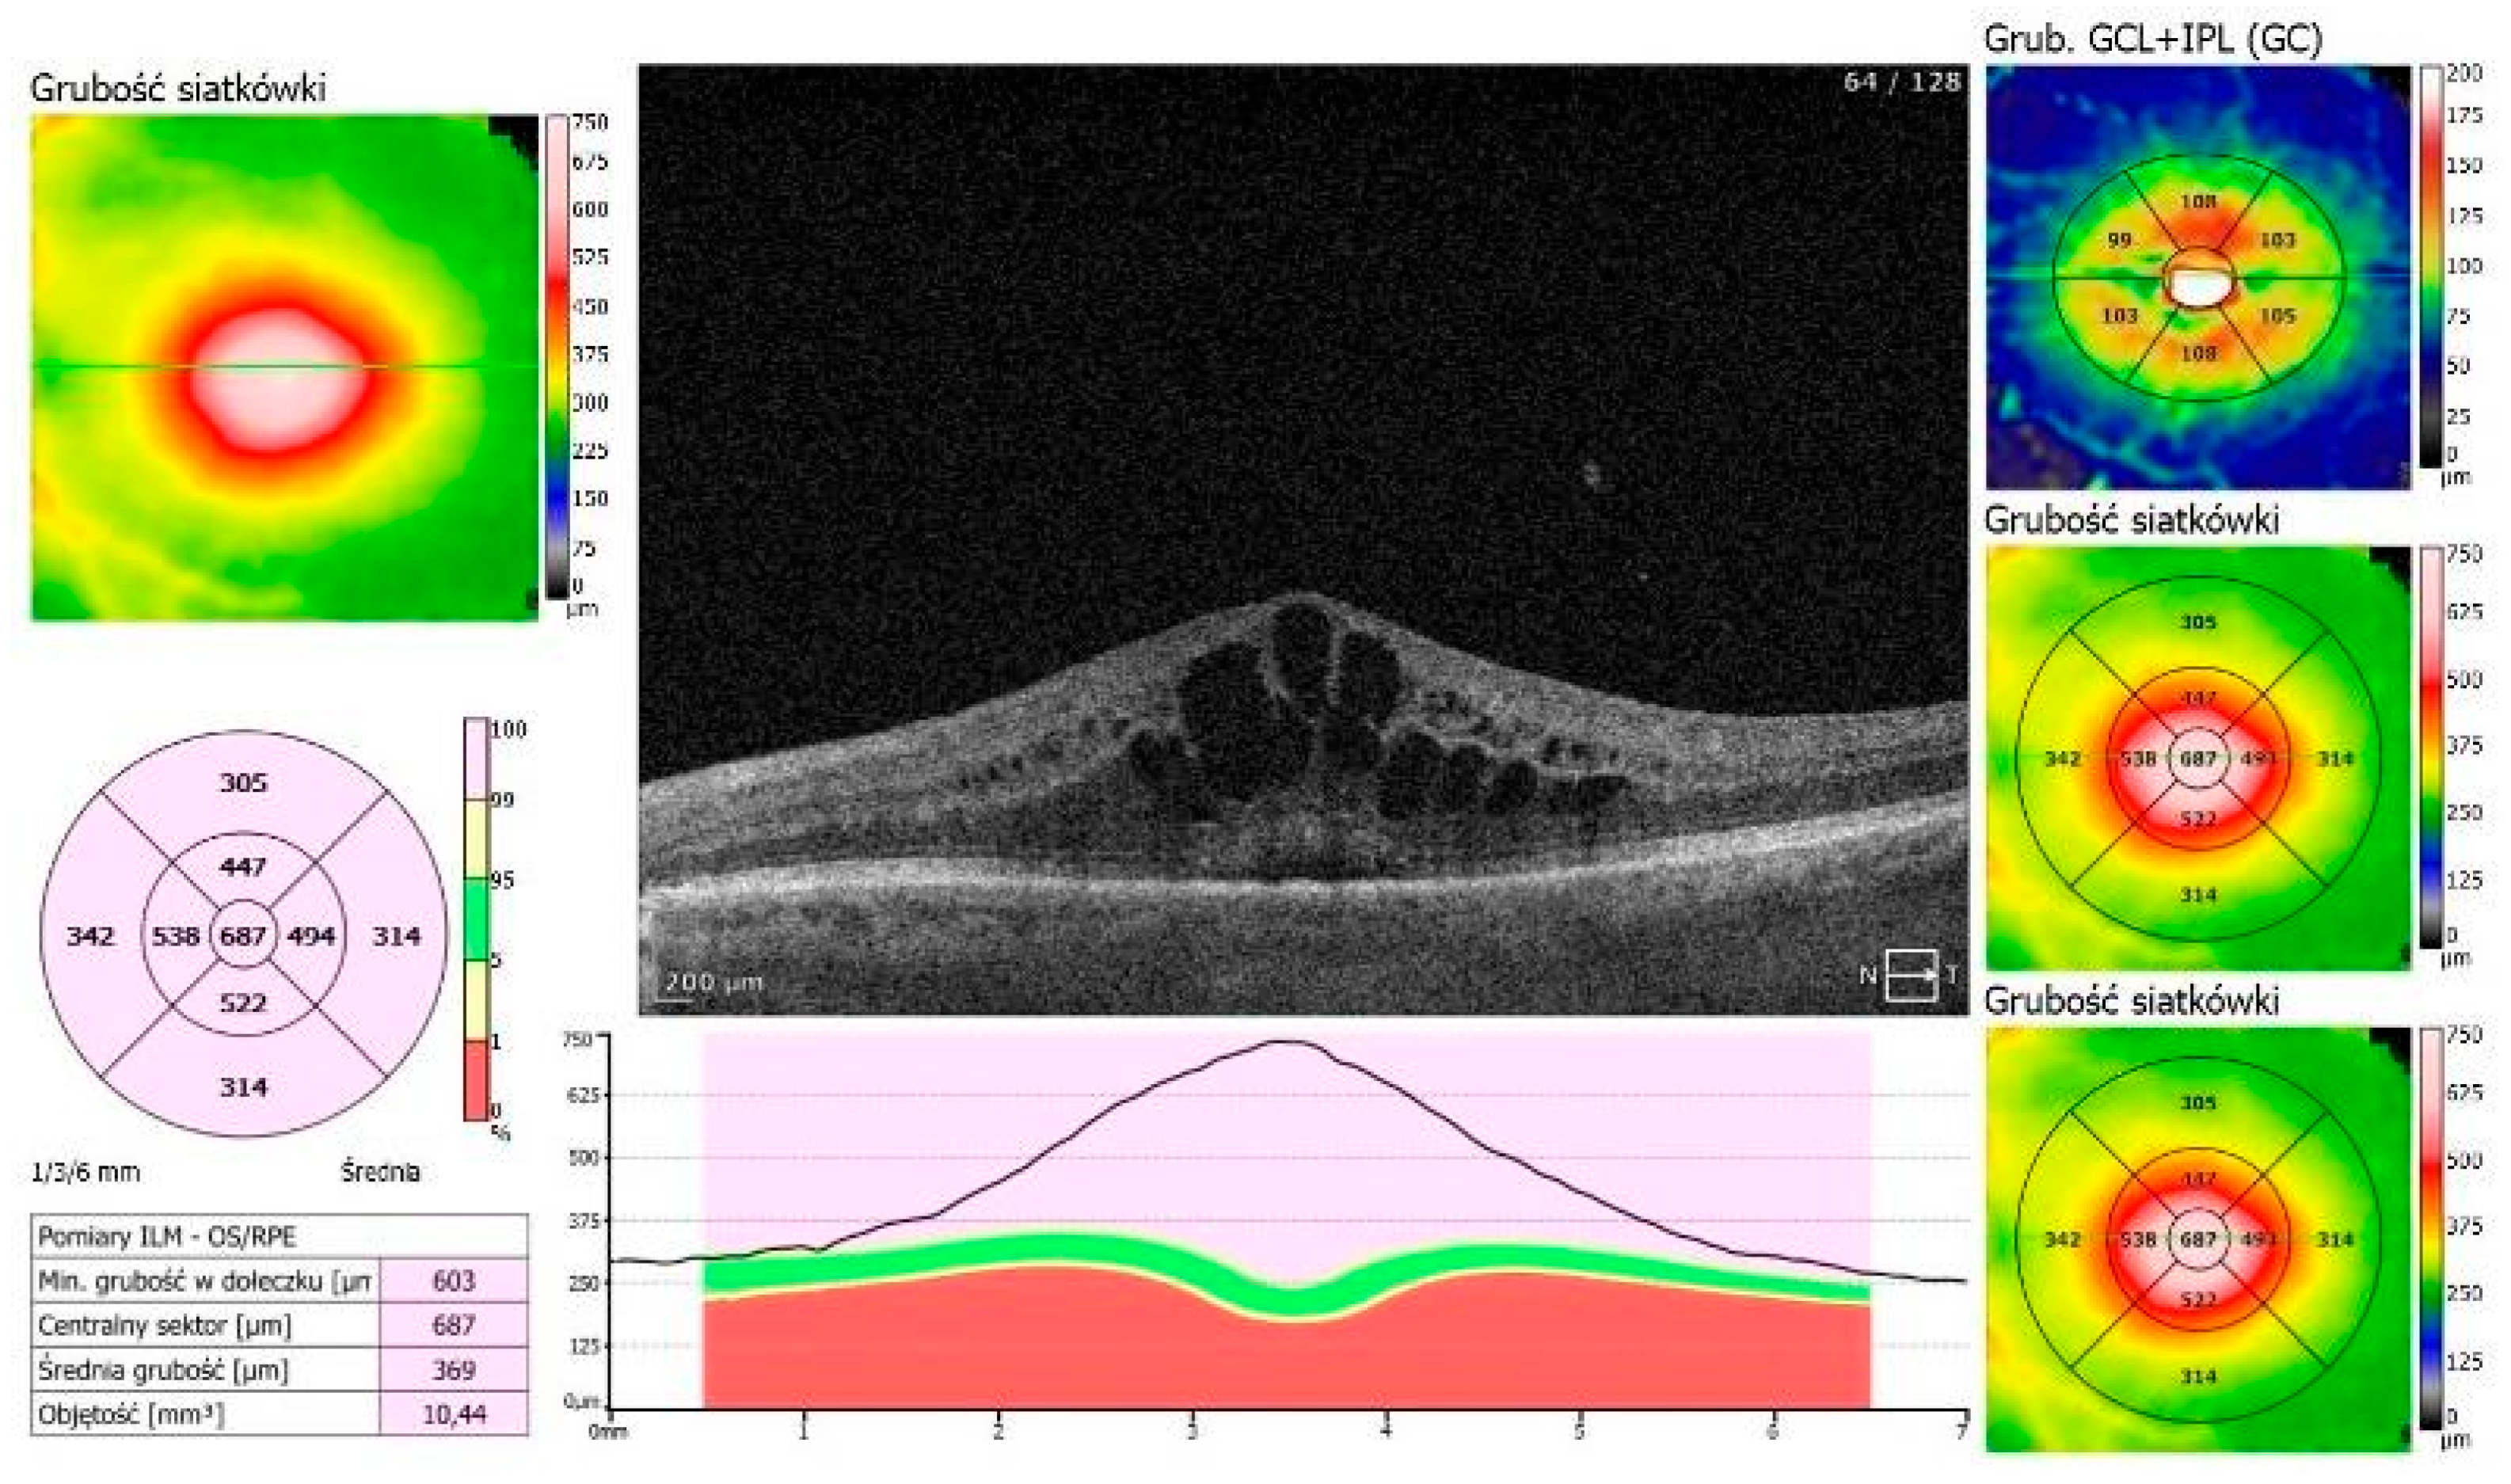

An 87-year-old Caucasian male was admitted to our clinic with sudden, painless vision loss of his left eye. His medical history was unremarkable except for uneventful cataract surgery in both eyes two months prior. Two months postoperatively, he developed macular edema in the left eye, which was confirmed on optical coherence tomography (OCT, SOCT-Copernicus, Revo NX, Software version 11.5.1, Optopol Technology Ltd., Zawiercie, Poland) (Figure 1). Treatment for PCME was initiated with topical pranoprofen and oral acetazolamide (250 mg twice a day).

Figure 1. PCME—Irvin–Gass Syndrome in the LE. Best corrected visual acuity (BCVA) = 0.4.